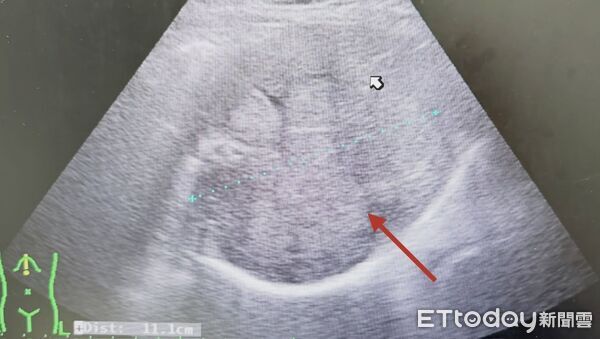

▲醫師以超音波一掃,發現患者的肝臟又被腫瘤塞爆了。(圖/張靖醫師授權提供,未經同意請勿任意翻攝)

有不少人以為腫瘤只要手術切除就畢業了,但若忽略術後追蹤,恐後果慘烈。胃腸肝膽科醫師張靖分享,近日收治一名上腹不適的患者,一照超音波赫然發現「無數的腫瘤」正密密麻麻地佔據整個肝臟。追問病史才發現,他雖然7~8年前曾開刀切除腫瘤,但術後自覺無礙就沒再回診,如今慘況連醫師都忍不住搖頭。